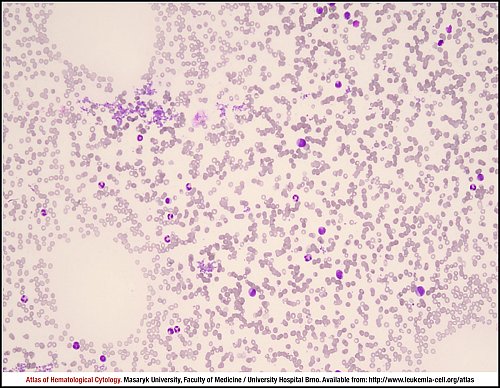

PB MGG (1000×)

Peripheral blood smear with a left shift: bare nuclei of a megakaryocyte with the rest of cytoplasm (yellow arrow), a myelocyte (red arrow), a band (blue arrow), a metamyelocyte (green arrow) and a fragment of megakaryocytic cytoplasm (black arrow).